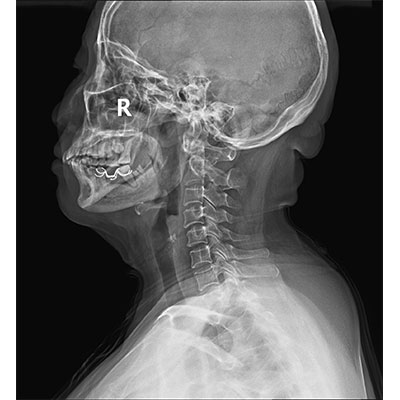

以微知形 為愛負責 微劑量 極速曝光 PLX8500E/F

● 短曝光、高熱容,拍片數量多、效率高。

● 輕松應對大型體檢中心高強度的拍片要求。

● 采用自主研發的技術,在保證優質圖像的前提下,大大降低X射線劑量,用心呵護醫護工作者及患者的健康。

● 短曝光時間,便于老年人、兒童、殘疾人進行臨床拍攝。避免這類群體因不能有效控制身體運動等因素造成的運動偽影,提高攝片質量及效率。